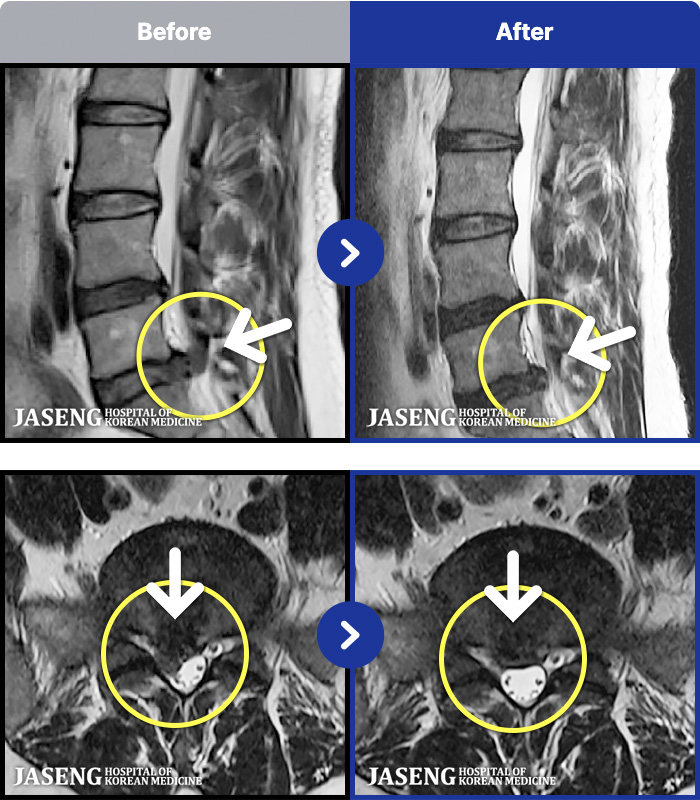

MRI ġ

1,240 MRI ũ ʸ Ȯϼ.